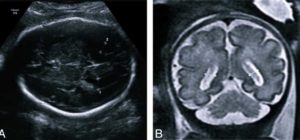

- Обнаружить болезнь у плода можно, начиная с 17-той недели беременности. Для диагностики врач проводит УЗИ брюшной полости матери;

- Вентрикуломегалия у грудничка подтверждается после проведения УЗИ головы;

С целью оценки развития головного мозга плода женщине выполняется процедура УЗИ. Это единственно достоверный метод диагностики патологии.

Вентрикуломегалией называют расширение боковых желудочков головного мозга. Уже на 17-й неделе вынашивания плода можно выявить патологию с помощью УЗИ. На полученных снимках явственно заметно увеличение пазух. Расширение, считающееся патологическим, составляет более 10 мм.

Анализ структур головного мозга у плода проводят во втором триместре, в период между 18 и 27 неделями беременности. В большинстве случаев патологические изменения обнаруживаются на плановом УЗИ. Диагноз также ставят на 30-33 недели беременности.

Первые признаки вентрикуломегалии у плода в период беременности могут быть выявлены на сроке 17-34 недели при проведение планового осмотра и УЗИ.